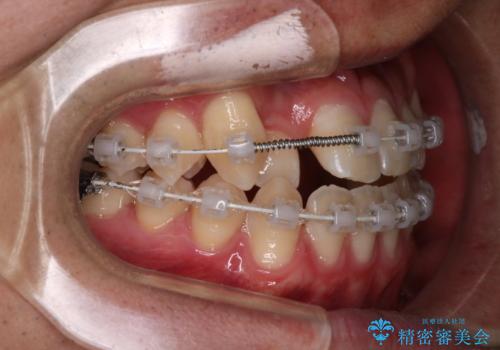

その点を考慮して、リンガルアーチを用いて奥歯を遠心移動し、前歯にIPR(歯と歯の間を削る処置)を行うことでスペースを作って歯並びを整えていく計画を立てました。

リンガルアーチを用いて奥歯を遠心移動し、前歯にIPR(歯と歯の間を削る処置)を行うことでスペースを作って歯並びを整えていく計画を立てました。